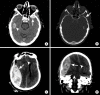

Intracranial hemorrhage is common and is caused by diverse pathology, including trauma, hypertension, cerebral amyloid angiopathy, hemorrhagic conversion of ischemic infarction, cerebral aneurysms, cerebral arteriovenous malformations, dural arteriovenous fistula, vasculitis, and venous sinus thrombosis, among other causes. Neuroimaging is essential for the treating physician to identify the cause of hemorrhage and to understand the location and severity of hemorrhage, the risk of impending cerebral injury, and to guide often emergent patient treatment. We review CT and MRI evaluation of intracranial hemorrhage with the goal of providing a broad overview of the diverse causes and varied appearances of intracranial hemorrhage.